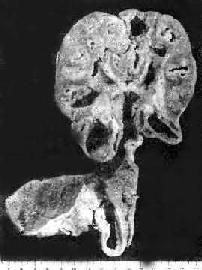

1. 肾结核病 最常见于20~40岁。男性多于女性。多为单侧性、双侧性肾结核的发病率约为10%。病变开始于肾皮、髓质交界处或乳头体内。初为局灶性结核病变,病变继 续扩大发展则发生干酪样坏死,破坏肾乳头而溃破入肾盂,成为结核性空洞。随着病变在肾内扩大蔓延,形成多数结核空洞,最后可使肾仅剩一空壳(图 18-15)。由于液化的干酪样坏死物可随尿液下行,常使输尿管膀胱感染。输尿管粘膜可发生溃疡和结核性肉芽组织形成,使管壁增厚、管腔狭窄,甚至阻 塞,结果常引起肾盂积水积脓膀胱三角区往往最先受累,形成溃疡,以后可侵及整个膀胱,可引起膀胱壁纤维化,使膀胱容积缩小(膀胱挛缩)。膀胱的溃疡和 纤维组织增生如影响到对侧的输尿管口,可使管口狭窄或失去正常的括约肌功能(关闭不全),造成对侧健肾引流不畅,最终可引起肾盂积水。结核菌也可逆行感染 对侧肾。

肾结核及输尿管结核

图18-15 肾结核及输尿管结核

肾实质内多数干酪样坏死灶及空洞形成;输尿管壁增厚,粘膜有多数结核结节及浅表溃疡形成